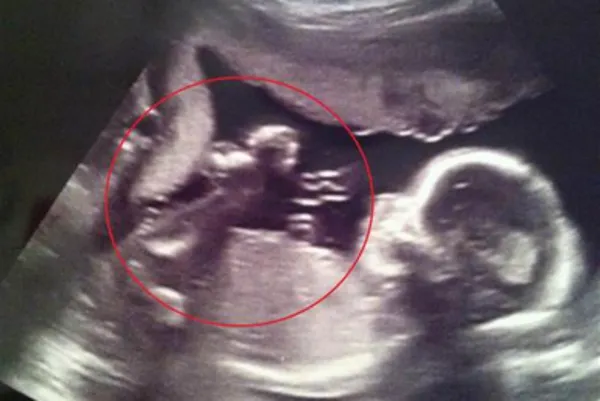

Charakterystyczne objawy owinięcia pępowiny na USG

Na obrazach USG można zauważyć kilka charakterystycznych objawów owinięcia pępowiny wokół szyi płodu. Do najczęstszych należą widoczne pętle pępowiny, które mogą być zlokalizowane w okolicy szyi. Dodatkowo, nietypowe położenie pępowiny oraz zmiany w przepływie krwi, które można ocenić za pomocą badania Dopplerowskiego, również mogą wskazywać na owinięcie. Te objawy są kluczowe dla lekarzy w diagnozowaniu i podejmowaniu dalszych działań w celu monitorowania stanu płodu.